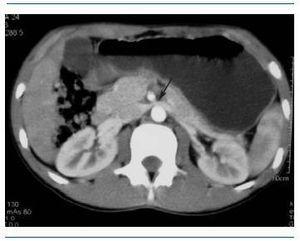

Paciente de 17 años con historia de tres años de evolución consistente en dolor lumbar y hematuria macroscópica después del ejercicio, con necesidad de transfusiones en cuatro ocasiones por anemia secundaria, llegando a tener hemoglobinas de 6,5 g/dl. Se realizan pruebas de coagulación, función renal, proteinuria y ecografía renal, con resultados normales; biopsia renal que muestra cambios sugestivos de membrana basal delgada; en abril de 2008 se realiza tomografía contrastada de abdomen que muestra compresión de la vena renal izquierda entre la arteria mesentérica superior y la aorta, hallazgo sugestivo de síndrome de Nutcracker que se confirma con la realización de cavografía y venografía renal, donde muestran área de compresión extrínseca en el tercio medio de la vena renal izquierda con drenaje colateral a través de la vena gonadal generando varicocele (figura 2). La manometría intravascular revela gradiente cavo renal de 5 mmHg. Con estos resultados, se decide manejo endovascular mediante colocación de stent en la vena renal izquierda. Durante el seguimiento del paciente, la hematuria macroscópica despareció a las seis semanas postratamiento.

Figura 2. Venografía renal con técnica de sustracción digital. Se observa marcada dilatación de la vena gonadal y el plexo pampiniforme izquierdo secundario a compresión de la vena renal causada por la arteria mesentérica superior, causando insuficiencia venosa.